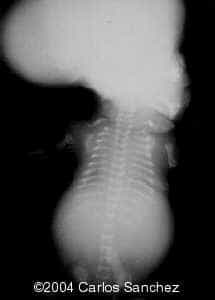

Postnatal radiograph:

td14

Platyspondyly:

td7